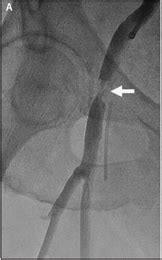

Clinicians were traditionally taught to use anatomic landmarks, x-ray, guidance, or the point of maximal impulse to maximize access into the CFA. However, modern ultrasound-guided access, especially using long access views, has rendered these techniques unnecessary. All nonvisualized femoral access techniques suffer from the same assumption—that the CFA is of average length and free of significant atherosclerosis. Ultrasound-guided access allows the operator to place the puncture in the most optimal location, minimizing the risk of intraprocedural and postprocedural complications. The puncture should be above significant atherosclerosis but low enough to avoid the risk of retroperitoneal bleeding. While short-axis ultrasound is highly effective for targeting the artery, it is less effective at confirming a precise location within the artery, thus increasing the risk of a high puncture.1 The FAUST trial demonstrated a 2% improvement in vascular complication rates with ultrasound-guided access.1 By incorporating long-axis ultrasound guidance, we aim to achieve even better outcomes by avoiding dangerous atherosclerotic plaques and ensuring puncture placement in the CFA over the femoral head (Figure 1).

VCDs still have significant failure rates. There are 3 main mechanisms by which failure occurs: 1) the anchor of the VCD catches on intra-arterial plaque, pushing the pledget through the arteriotomy into the vessel; 2) the anchor catches on the back wall, pulling that wall or plaque to the front and sealing the vessel; and 3) the anchor is pulled through or never placed into the vessel, resulting in deployment external to the arteriotomy. By directly visualizing the closure process, the goal is to minimize these 3 mechanisms of failure, thus improving the safety of nonradial access while also allowing for recognition of closure failure and their mechanisms, enabling intervention on the table before complications become more significant (Figure 2).